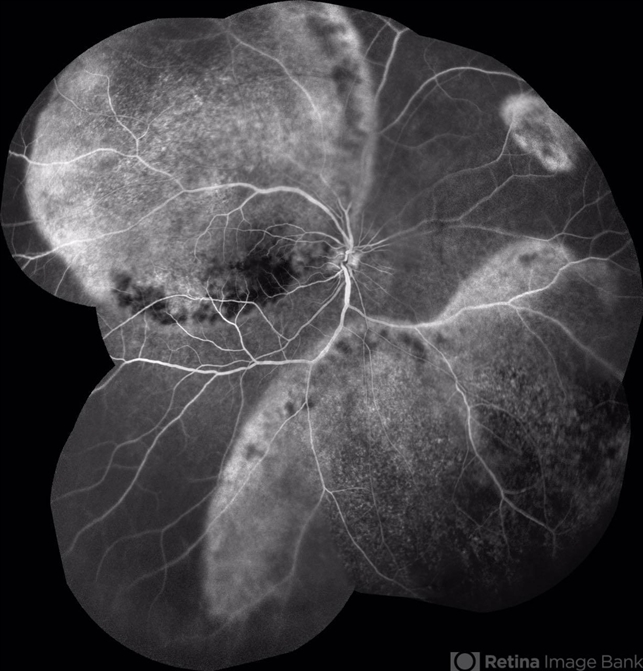

- acute syphilitic posterior placoid chorioretinitis

- Intravenous Fluorescein angiography

- 66-year-old woman with acute visual acuity loss.